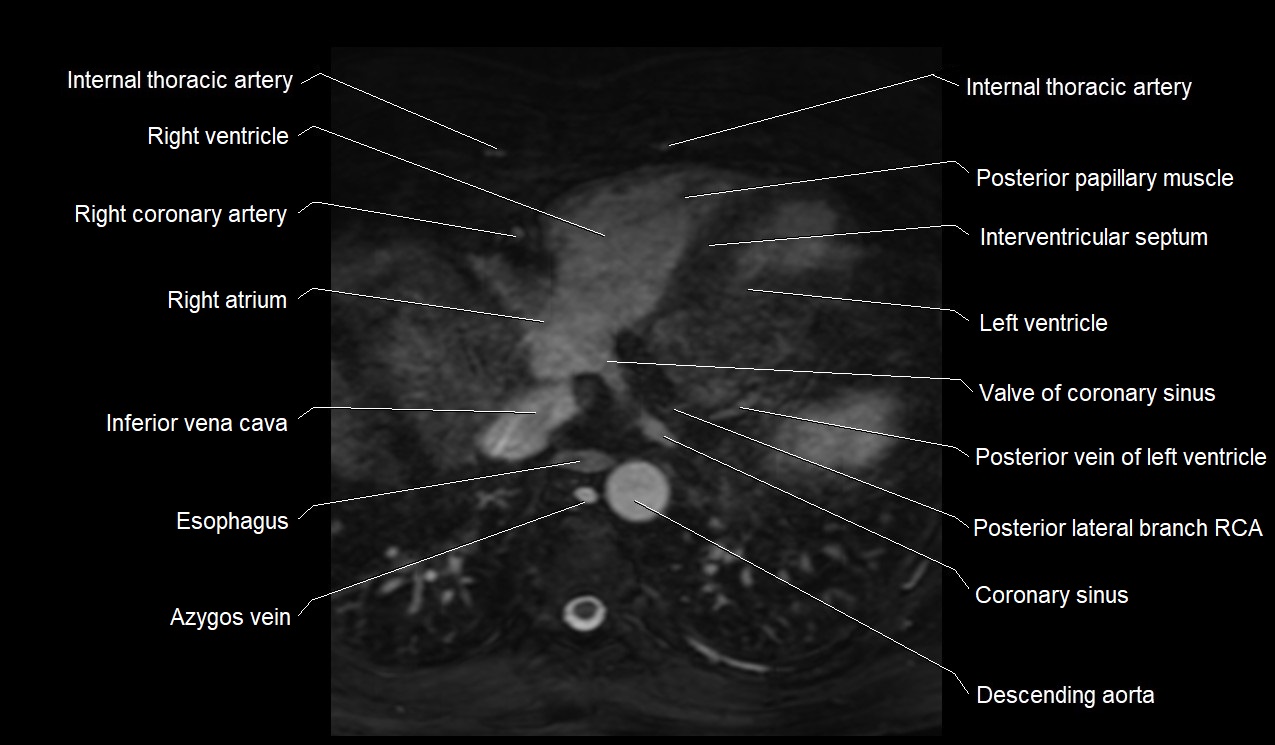

CT images